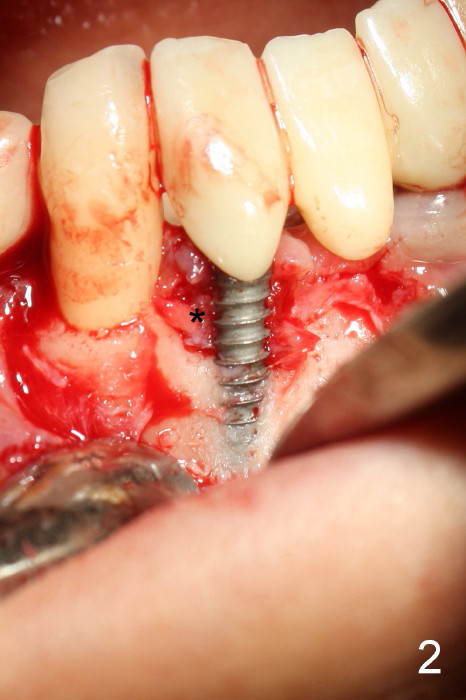

The patient has had chronic pain and swelling associated with the implant at the site of #26 (Fig.1). The extent of implant thread exposure is shown in Fig.2 after flap reflection; inflammatory granulation tissue is present around the most coronal threads (*, one year post cementation). Following debridement and Clindamycin soaking, allograft is placed around the exposed threads; a titanium mesh is used to contain the graft (Fig.3). The flap is closed with tension in spite of the periosteum being underscored. The patient develops moderate to severe ecchymosis postop.